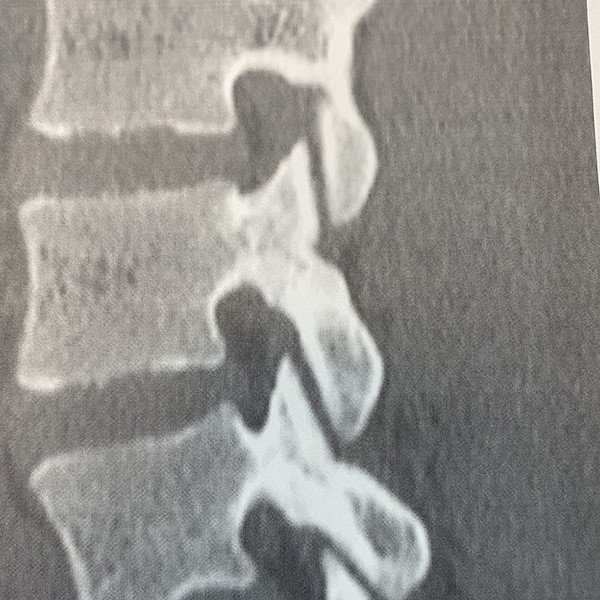

2ヶ月後のCT画像